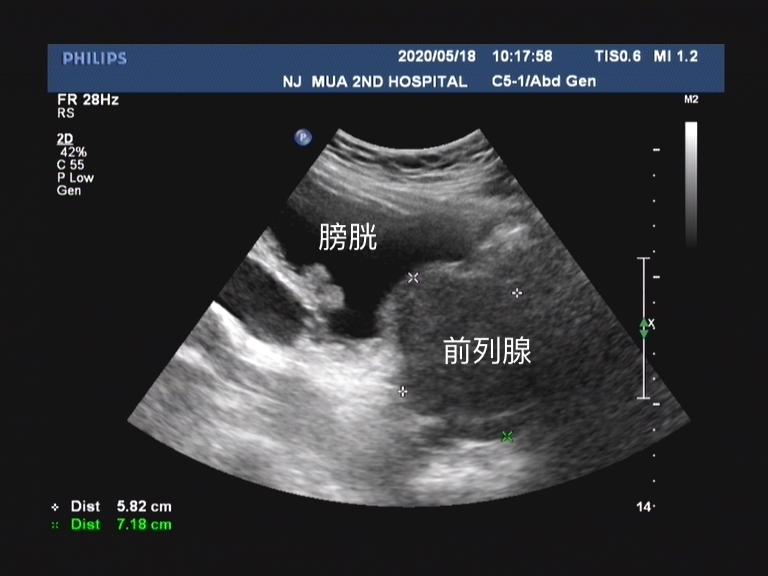

从PSA的分泌来源中我们不难看出,随着前列腺体积增大, 前列腺增生组织也会分泌PSA 。所以对于很多老年男性患者,虽然PSA水平增高,但是在核磁共振检查和前列腺穿刺活检中都最终证实并不是前列腺癌。

前列腺特异性抗原密度(PSAD)是测算血清总PSA值与前列腺体积的比值,正常值≤0.15。比值越高意味着越有可能为具有临床意义的前列腺癌。